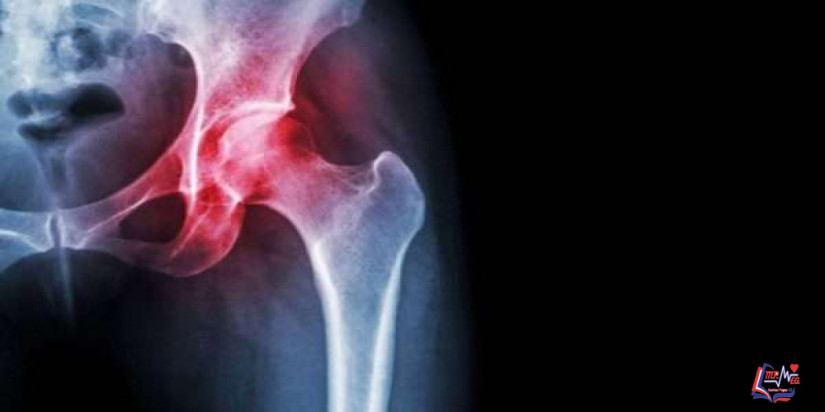

كسر الورك Hip Fracture

كسر الورك من الإصابات الخطيرة التي تحدث مع التقدم في العمر، فمن الممكن أن يكون كسر الورك سبباً من أسباب الوفاة.